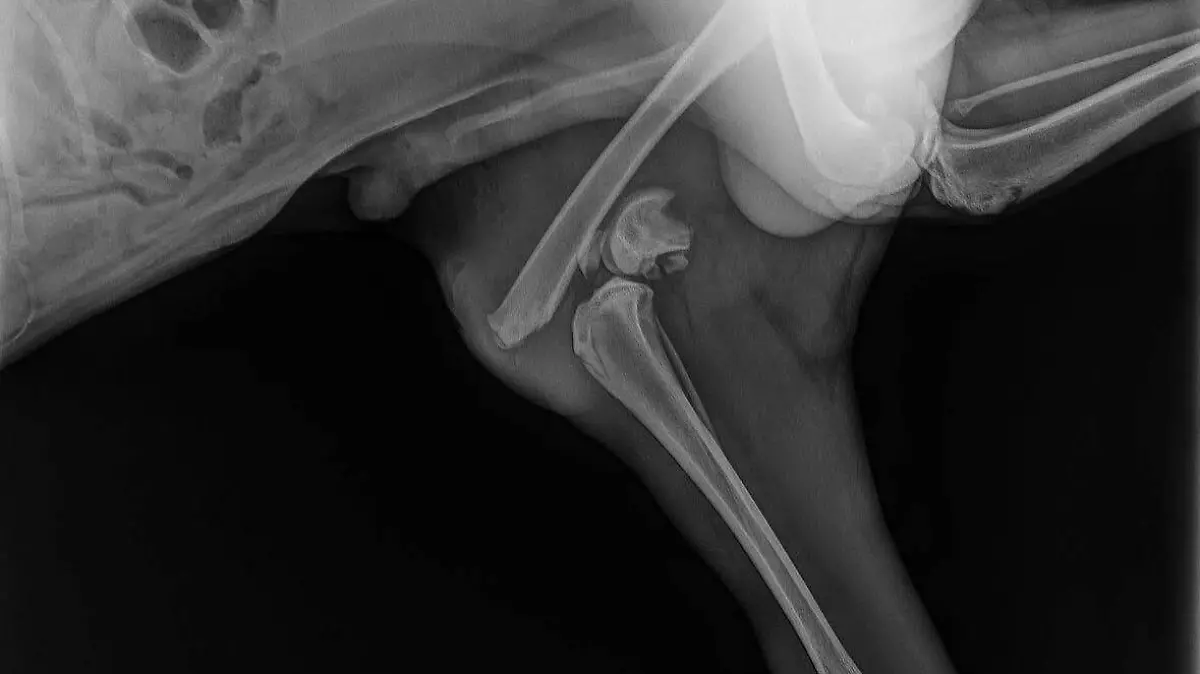

Dobby tendrá dos operaciones tras haber sido atropellado cerca de la colonia Los Salazares; su rescatista también busca adoptantes